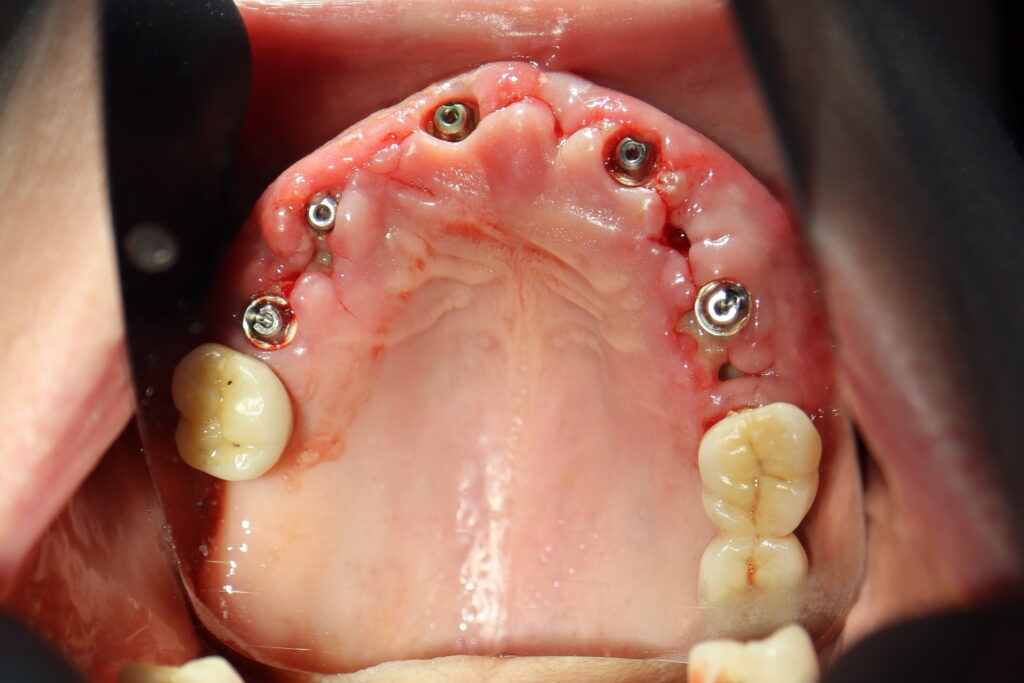

Процесс работы

Что было сделано:

На верхней челюсти были сняты старые мостовидные протезы и удалены зубы, которые находились в неудовлетворительном состоянии.

Установлены 5 имплантантов Straumann BLT и сняты оттиски. Спустя 6 дней на верхней челюсти зафиксирован протез из пластмассы, армированный металлической балкой с опорой на 5 дентальных имплантатов. Ранее у пациента уже были установлены 3 имплантата Straumann.

При постоянном протезировании протез будет зафиксирован на 8ми имплантатах.

процесс имплантации

Это фото может содержать тяжелый для восприятия контент